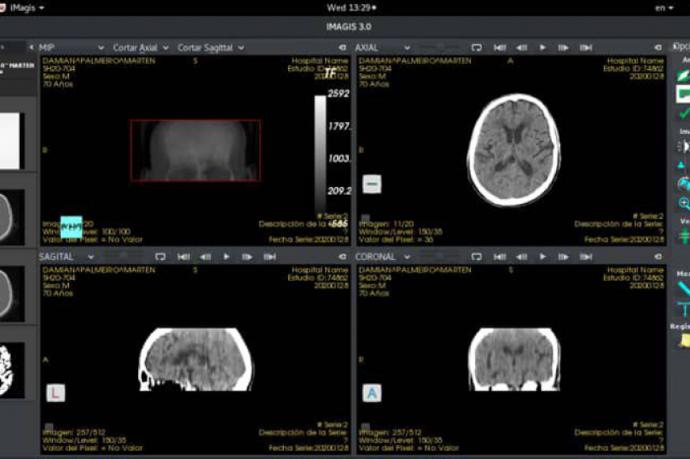

Imagis moderniza servicios de Radiología en el oriente de Cuba

Creada por el Centro de Biofísica Médica de la Universidad de Oriente, en Santiago de Cuba, la actual versión de la plataforma Imagis, para visualizar, transmitir y almacenar imágenes médicas, favorece la digitalización de los servicios de radiología en la región oriental del país.